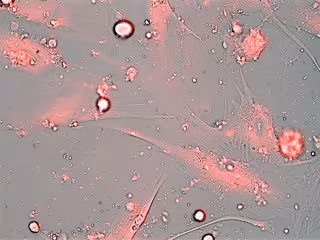

Los investigadores han evaluado la utilidad de los nuevos nanodispositivos en cultivos celulares primarios derivados de pacientes con el síndrome de envejecimiento acelerado Disqueratosis Congénita (DC). Dichos cultivos presentan un alto porcentaje de senescencia, caracterizada por elevados niveles de actividad de betagalactosidasa, una enzima característica del estado senescente. "Las células envejecidas sobreexpresan esta enzima; las nanopartículas que hemos diseñado se abren ante su presencia, liberando su contenido para eliminar las células senescentes, prevenir su deterioro o incluso reactivarlas para su rejuvenecimiento", apunta Murguía.